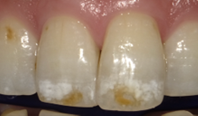

治療前(ビフォー)

薬剤

術野が唾液や水でぬれないように治療を行っています